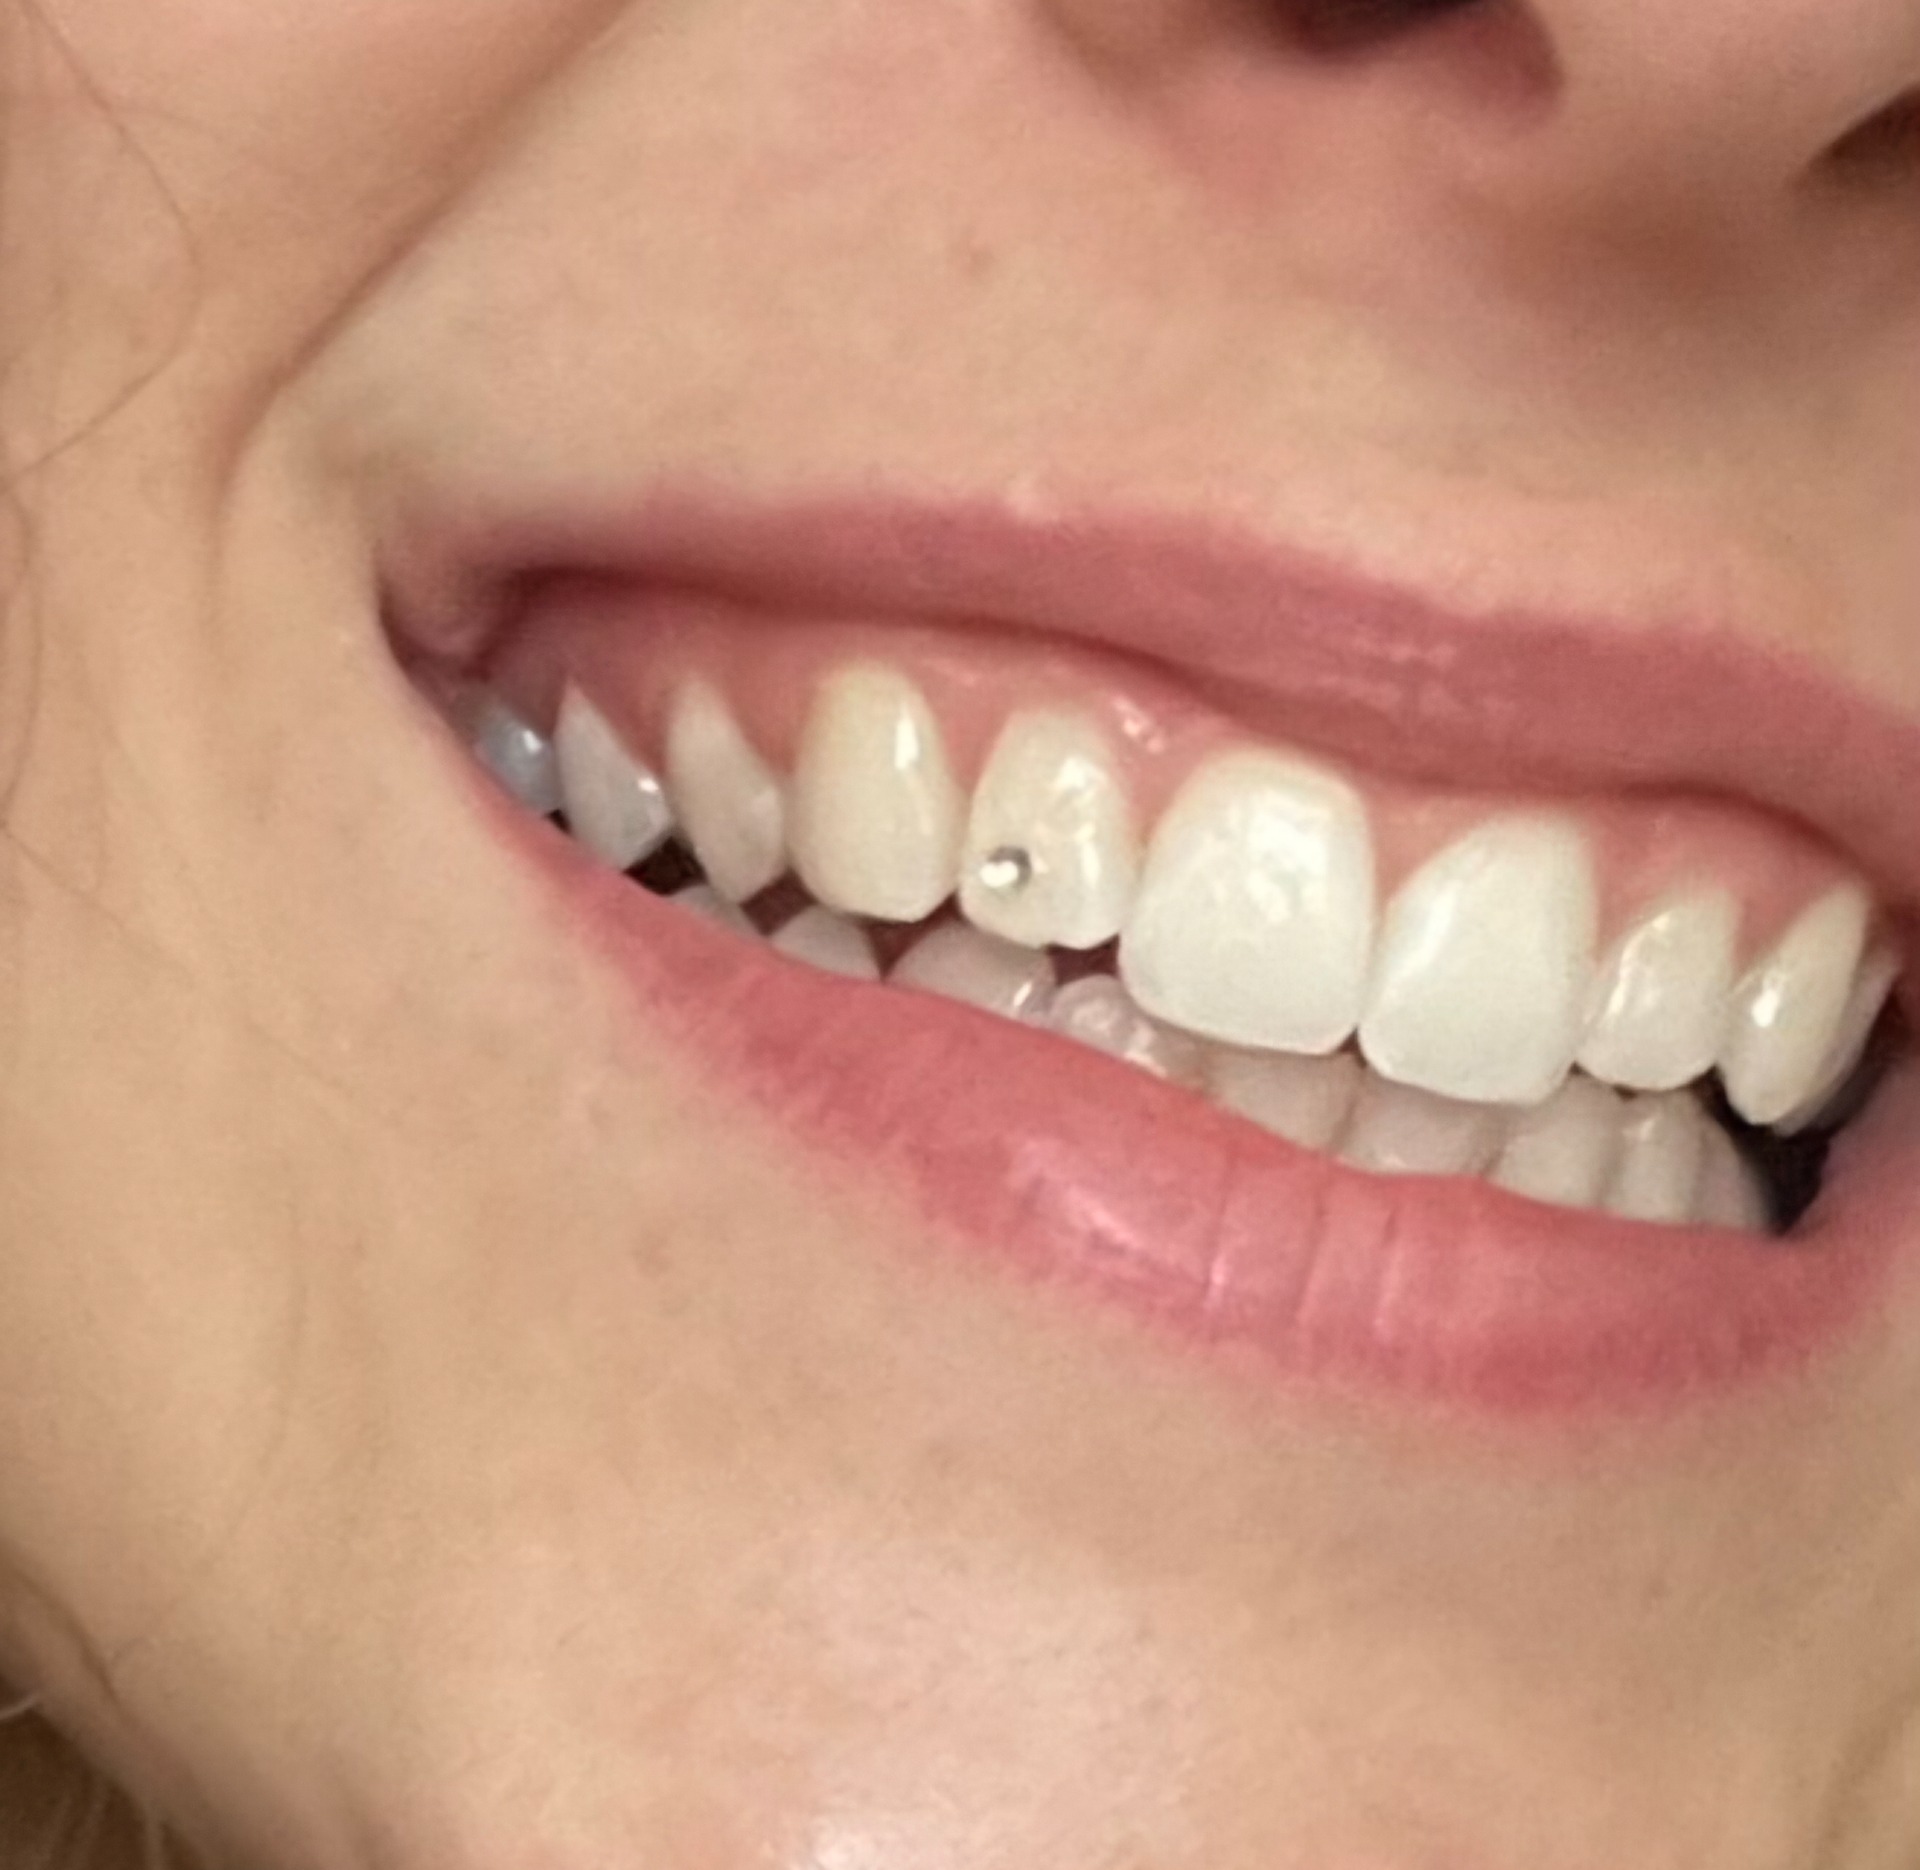

Fogékszer felhelyezés.